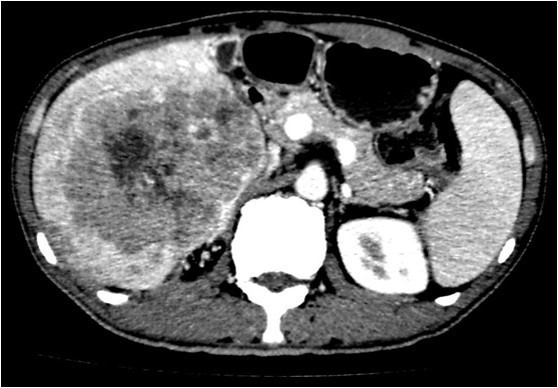

体查:未见阳性体征 实验室检查: WBC 7.24× 109/L, N 48.1%, Hb 159g/L, PLT 117× 109 /L ,PT 12.5s ; HBsAg+, HBcAb+,HBeAg+;HBV-DNA5.33× 106 IU/mL ALT 240 U/L, AST 154 U/L, ALB 36.9g/L, TBIL 13.1umol/L AFP 6270 ug/L ICG 15分钟滞留率 4.5%;Child-Pugh A级 CT提示肝S5、S6肝细胞癌并门静脉右支癌栓形成

诊断: • 肝细胞癌 • 门静脉右支癌栓 治疗:右半肝切除、门静脉取癌栓、胆囊切除术 术后病理: • 肝细胞癌,梁索型,II级,癌旁组织呈门脉性肝硬化改变 • 门静脉内组织呈现肝细胞癌改变伴坏死,符合癌栓改变